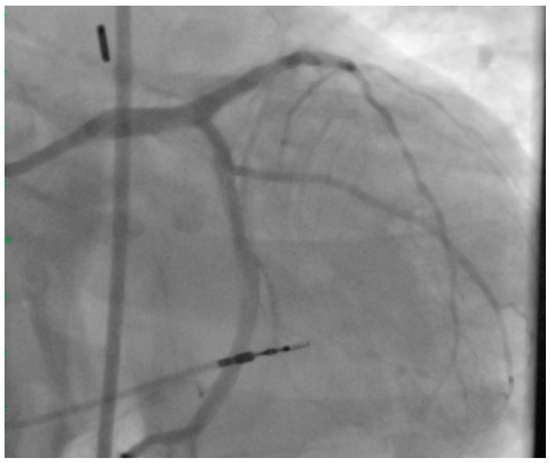

2. Left Main PCI

4. Achieving Adequate Left Main Minimal Luminal Area

5. Atherectomy in UPLM PCI